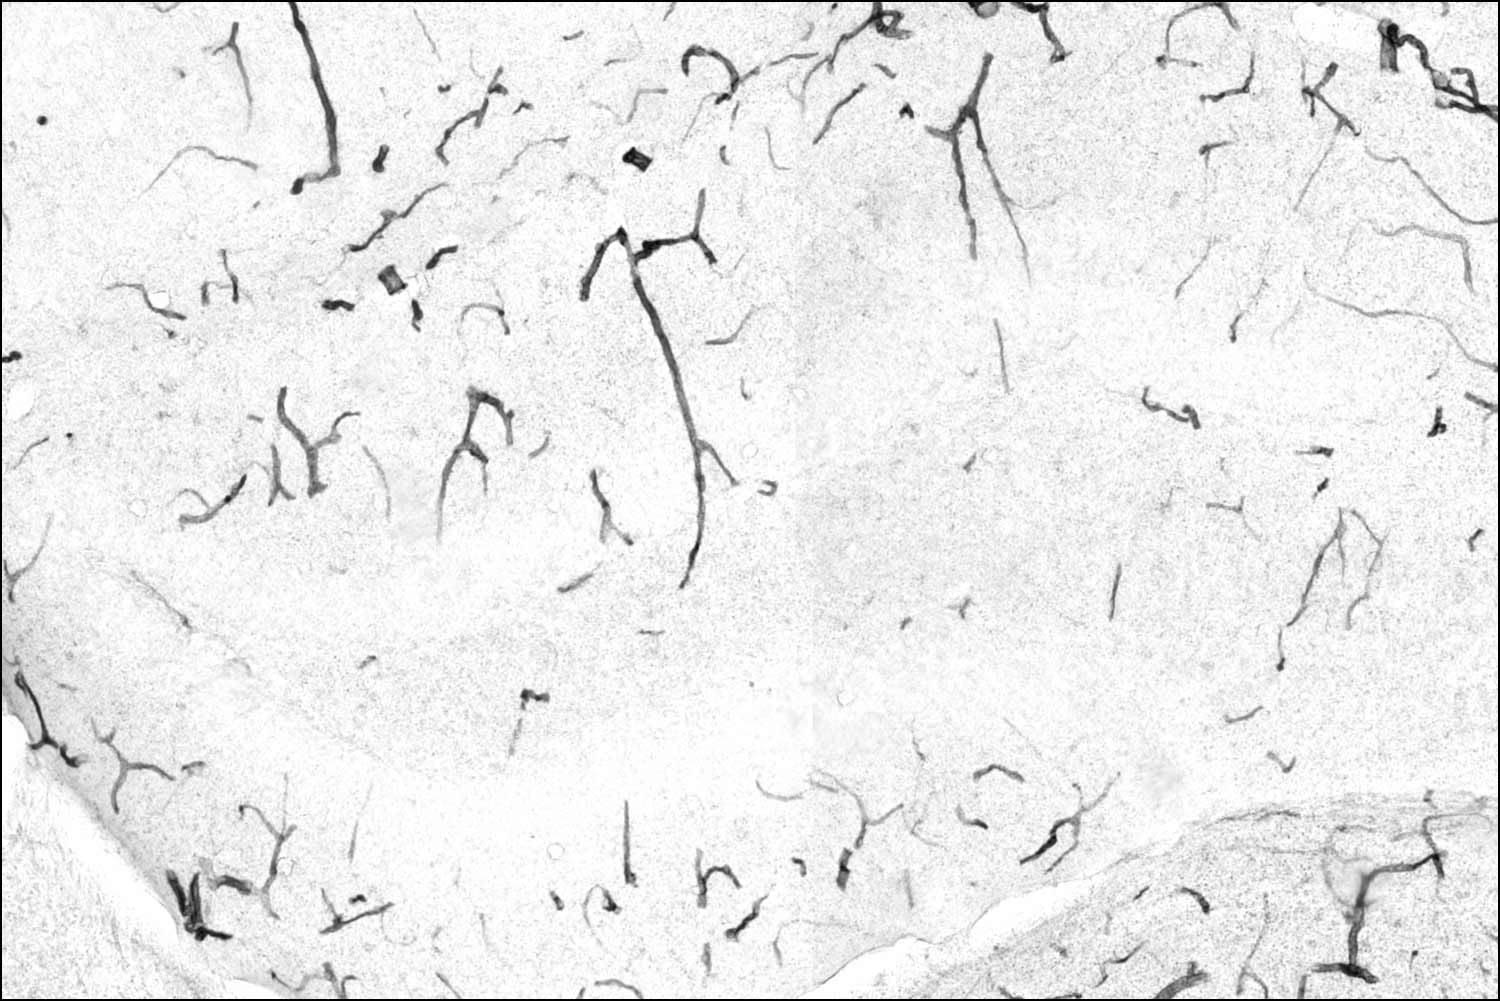

Para comprender la magnitud de este descubrimiento, debemos asomarnos a la microanatomía de la frontera cerebral. La BHE es una interfaz vascular altamente selectiva que separa el cerebro de la circulación sistémica, formada por un mosaico celular inexpugnable: células endoteliales microvasculares cerebrales (BMEC), astrocitos y pericitos.

A diferencia de otros vasos sanguíneos, las BMEC carecen de poros o fenestraciones. Están selladas por uniones estrechas (compuestas por proteínas como claudinas y ocludinas), que restringen severamente el paso de sustancias, permitiendo solo la entrada de nutrientes esenciales y orquestando la expulsión meticulosa de neurotoxinas como el amiloide-beta.

El principal mediador de esta degradación no es un invasor externo, sino una enzima propia que se acumula patológicamente con la edad: la TNAP, anclada a la membrana de las células endoteliales por un resto lipídico.

No obstante, al envejecer, los mamíferos acumulan niveles tóxicos y fuera de lugar de esta misma enzima en la superficie de los microvasos cerebrales. Este exceso enzimático actúa como un óxido biológico que desmantela las proteínas que unen a las células, socavando los cimientos de la barrera hematoencefálica y disparando su permeabilidad. El equipo de UCSF demostró de forma concluyente que ratones jóvenes, genéticamente modificados para sobreexpresar TNAP en su barrera cerebral, perdían rápidamente sus capacidades cognitivas, confirmando que la acumulación de esta proteína es un artífice directo de la senescencia mental.